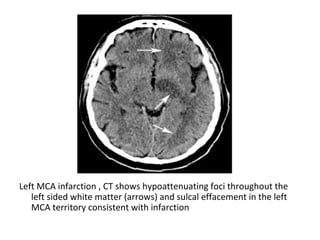

Left MCA infarction , CT shows hypoattenuating foci throughout the

left sided white matter (arrows) and sulcal effacement in the left

MCA territory consistent with infarction

-MCA infarction : on CT

an area of

hypoattenuation

appearing within six

hours is highly specific for

irreversible ischemic

brain damage

-The reason we see

ischemia on CT is that in

ischemia cytotoxic edema

develops as a result of

failure of the ion-pumps ,

these fail due to an

inadequate supply of

ATP , an increase of brain

water content by 1% will

result in a CT attenuation

decrease of 2.5 HU